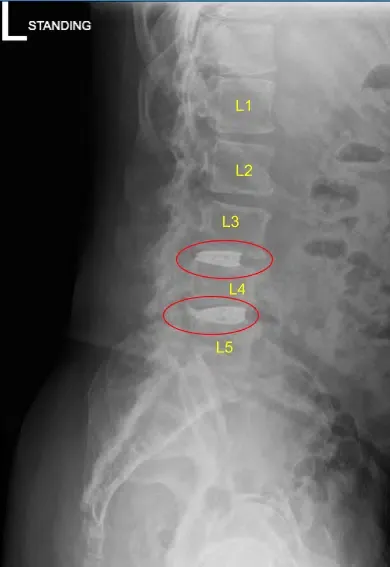

La resonancia magnética y la tomografía computarizada de la columna lumbar mostraron una grave ruptura degenerativa del espacio discal en L3-L4 y L4-L5, por lo que se les ofreció una cirugía para el dolor discogénico. Se explicaron extensamente los riesgos y posibles beneficios de la cirugía al paciente.

El espacio del disco se estrecha en L3-L4 y L4-L5

Protuberancia discal y artropatía facetaria

Firmaron el consentimiento informado y fueron llevados al quirófano para el procedimiento mencionado. Los hallazgos de la radiografía preoperatoria de la columna lumbar se muestran arriba y los pacientes también se sometieron a una tomografía computarizada preoperatoria (TAC) que se muestra arriba.